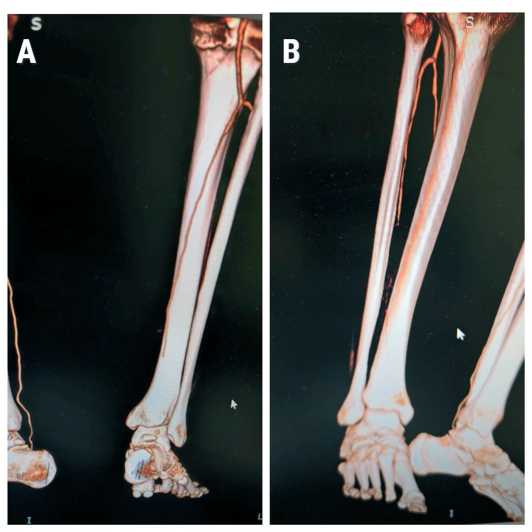

При дообследовании выявлена окклюзия всех артерий левой голени и стопы с типичными штопорообразными коллатералями, некротическая рана переднего отдела левой стопы после предшествующей хирургической обработки по месту жительства (рис. 9–7).

Рис. 7A, B . Предоперационная КТ-ангиография (вид на артерии правой голени и стопы сзади и спереди): видна окклюзия артерий в н/3 голени и стопы

Fig. 7A, B. Preoperative CT angiography (posterior and anterior views of the arteries of the right lower leg and foot): showing occlusion of the arteries in the distal third of the lower leg and foot